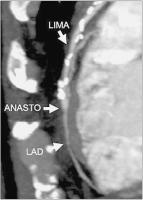

Bypässe - MPR - MIP

Abbildung 2b: Zur Beurteilung der Durchgängigkeit von Bypässen eignen sich vor allem MPR- (Multiplanare Reformation) und MIP-(Maximum Intensity Projection) Rekonstruktionen. Hier ebenso Darstellung eines an die LAD anastomosierten LIMA-Bypasses.